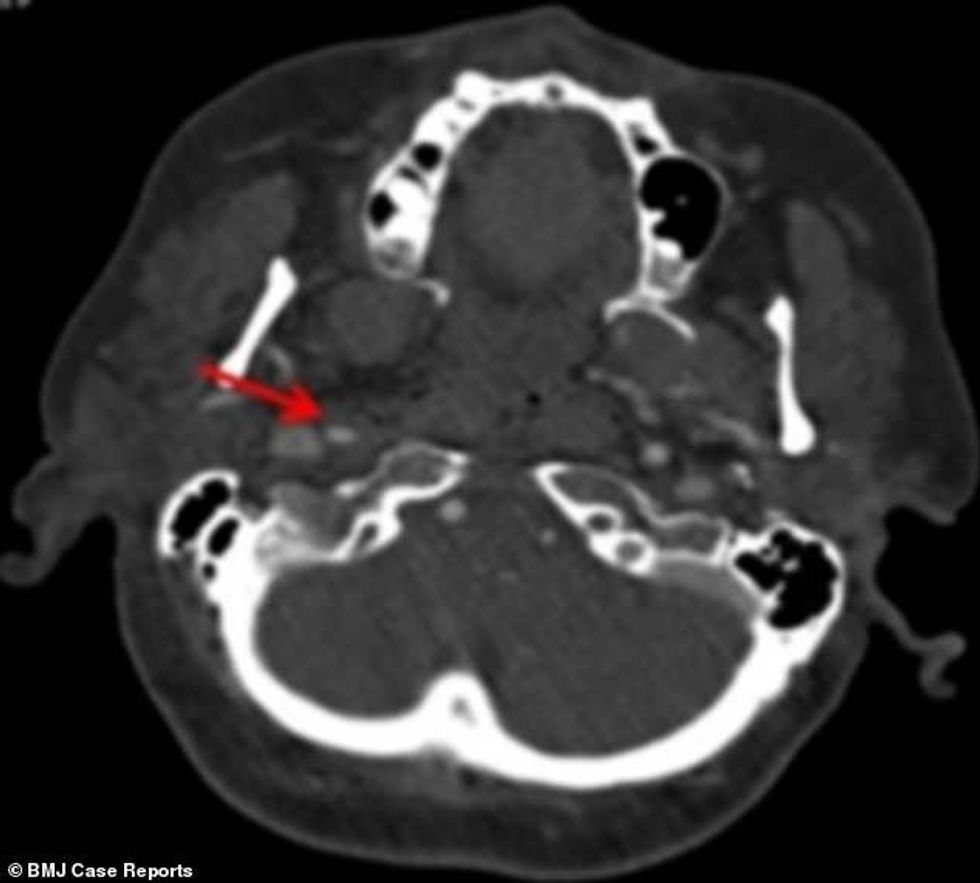

Vizitën e parë e bëri pas dy javësh, kur kapakët e syve po i mbylleshin vet, ndërsa njerëzit i shihte në forma dhe madhësi të ndryshme. Fotografimi me rreze X, ka treguar se i është shkëputur arteria që ia furnizon trurin me gjak dhe oksigjen.